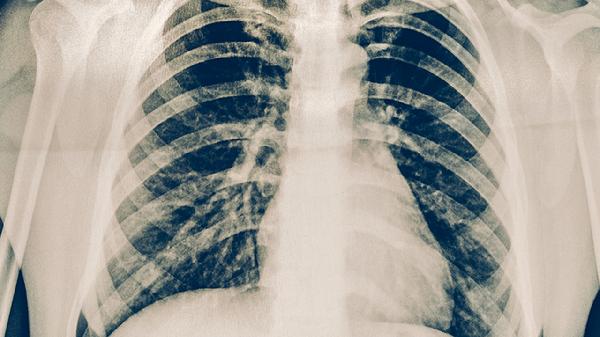

肺结核需遵医嘱使用异烟肼片、利福平胶囊、吡嗪酰胺片、乙胺丁醇片、链霉素注射剂等抗结核药物联合治疗。肺结核是由结核分枝杆菌感染引起的慢性传染病,主要经呼吸道传播,典型症状包括咳嗽、咯血、午后低热等,需规范用药6-9个月。

肺结核患者除规范用药外,应保持充足营养摄入,多食用高蛋白食物如鸡蛋、牛奶、瘦肉等,适量补充新鲜蔬菜水果。治疗期间需严格戒烟戒酒,避免劳累,保证每日8小时睡眠。定期复查胸部影像学和痰菌检查,密切观察药物不良反应,出现皮肤黄染、持续呕吐或视力变化应及时就医。完成全程治疗后仍需随访2年,防止复发。